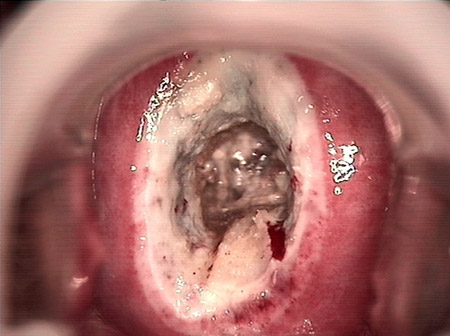

婦科leep錐切手術 CIN2-3

• CIN 2-3 leep術后CIN 2-3 leep術后